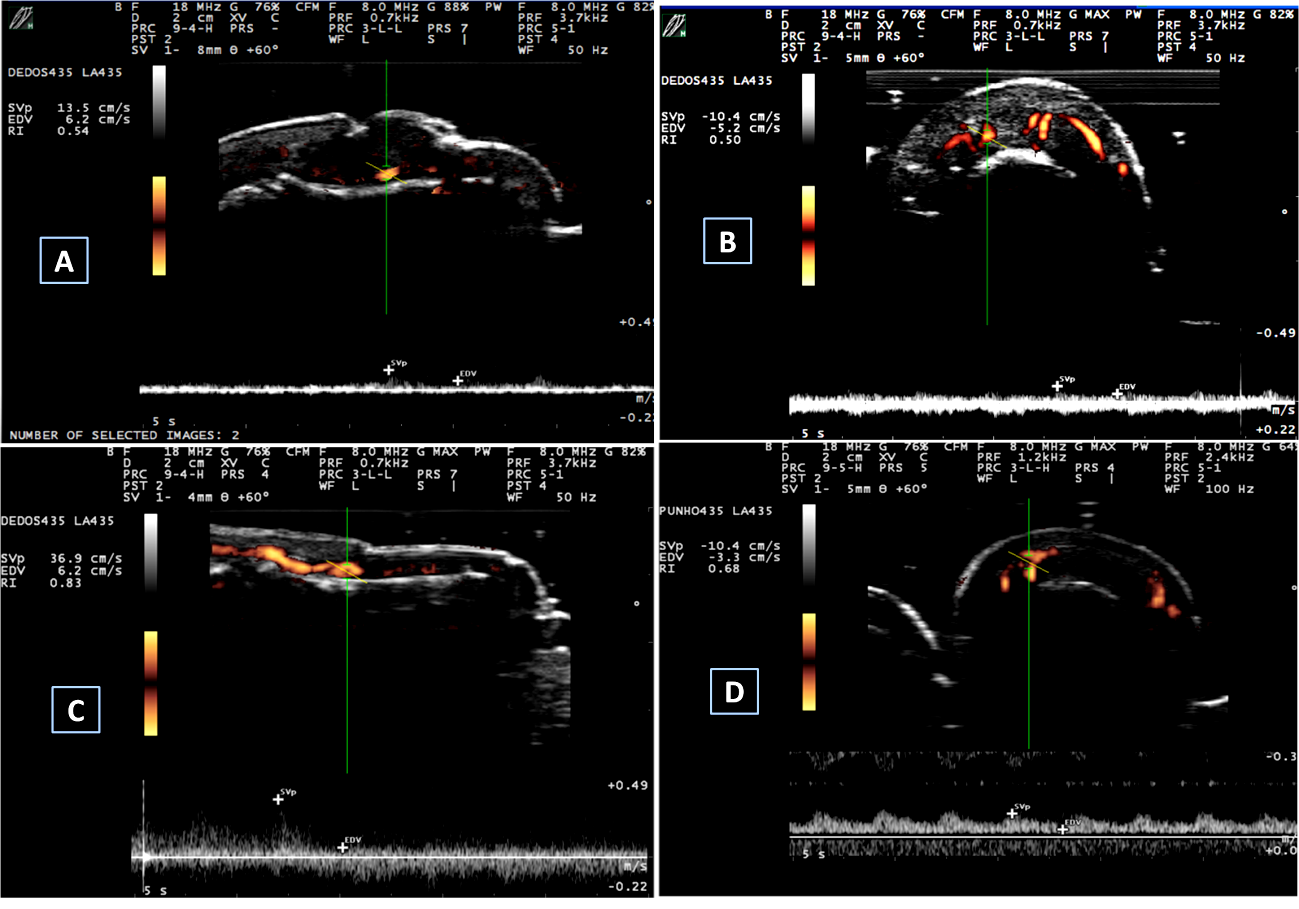

Nail abnormalities detected by US were graded with both GS and PD techniques. Nail abnormalities observed in the GS were semi-quantitatively graded from 0 to 3, as follows: GS0-preserved three-layered nail pattern; GS1-mild abnormality in the three-layered nail pattern or one sinuosity or nail loss; GS2-intense abnormality in the three-layered nail pattern, still preserving some segments of the nail, more than one sinuosity or nail loss; and GS3- total loss of the three-layered nail pattern, thickening of all the nail bed with loss of the eco texture or the nail insertion point (≥2.5 mm) (Figure 1). The nail bed (distance between the ventral plate and the bone margin of the distal phalanx) was measured in both the longitudinal plane (longitudinal mNGS, mm) and the transversal plane (transversal mNGS, mm). Nail PD abnormalities (PD0-3) were graded to measure the presence and intensity of nail enthesitis as follows: PD0: there is no in the nail bed flow; PD1: presence of 1 point or 25% of the PD signal especially at the insertion point of the nail; PD2: presence of <50% of the PD signal especially at the insertion point of the nail; PD3: presence of >50% of PD signal especially at the insertion point of the nail (Figure 2). sD was used to measure RI in the nail bed in both the longitudinal plane and the transversal plane (Figure 3).

Figure 3 Spectral Doppler measurements.

A and B: spectral Doppler measurements in a PsA patient. (A) Longitudinal spectral Doppler – RI=0.54; (B) Transversal spectral Doppler – RI=0.50; C and D: spectral Doppler measurements in a control individual. (C) Longitudinal spectral Doppler – RI=0.83 and D. Transversal spectral Doppler – RI=0.68.